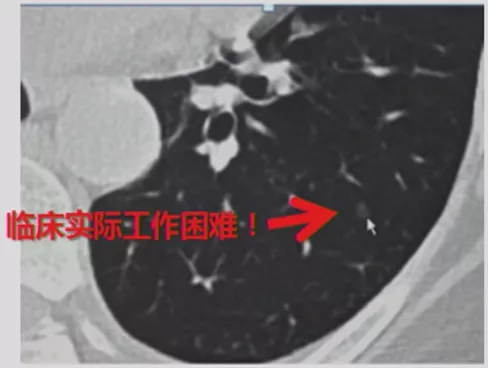

临床困境

根据NLST试验研究数据发现,尽管肺结节检出率高,但是现在通过大型筛查发现,仅有一小部分(约4%)是恶性病变。那么问题来了,临床发现的大量肺结节患者,如何知道哪些病人是在4%以内?这是临床医生难以判断之处。

如上图所示,一般来说这么小的病灶我们可能忽略,但这个病人做了手术,不仅是恶性肿瘤,而且是微浸润腺癌。实际上我们在临床上要把这么多结节甄别出来,是十分具有挑战性的。病人一旦患有肺结节,也面临着很多问题,比如焦虑、心理压力等。所以我们既不能过度诊断,但也不能延误诊断。